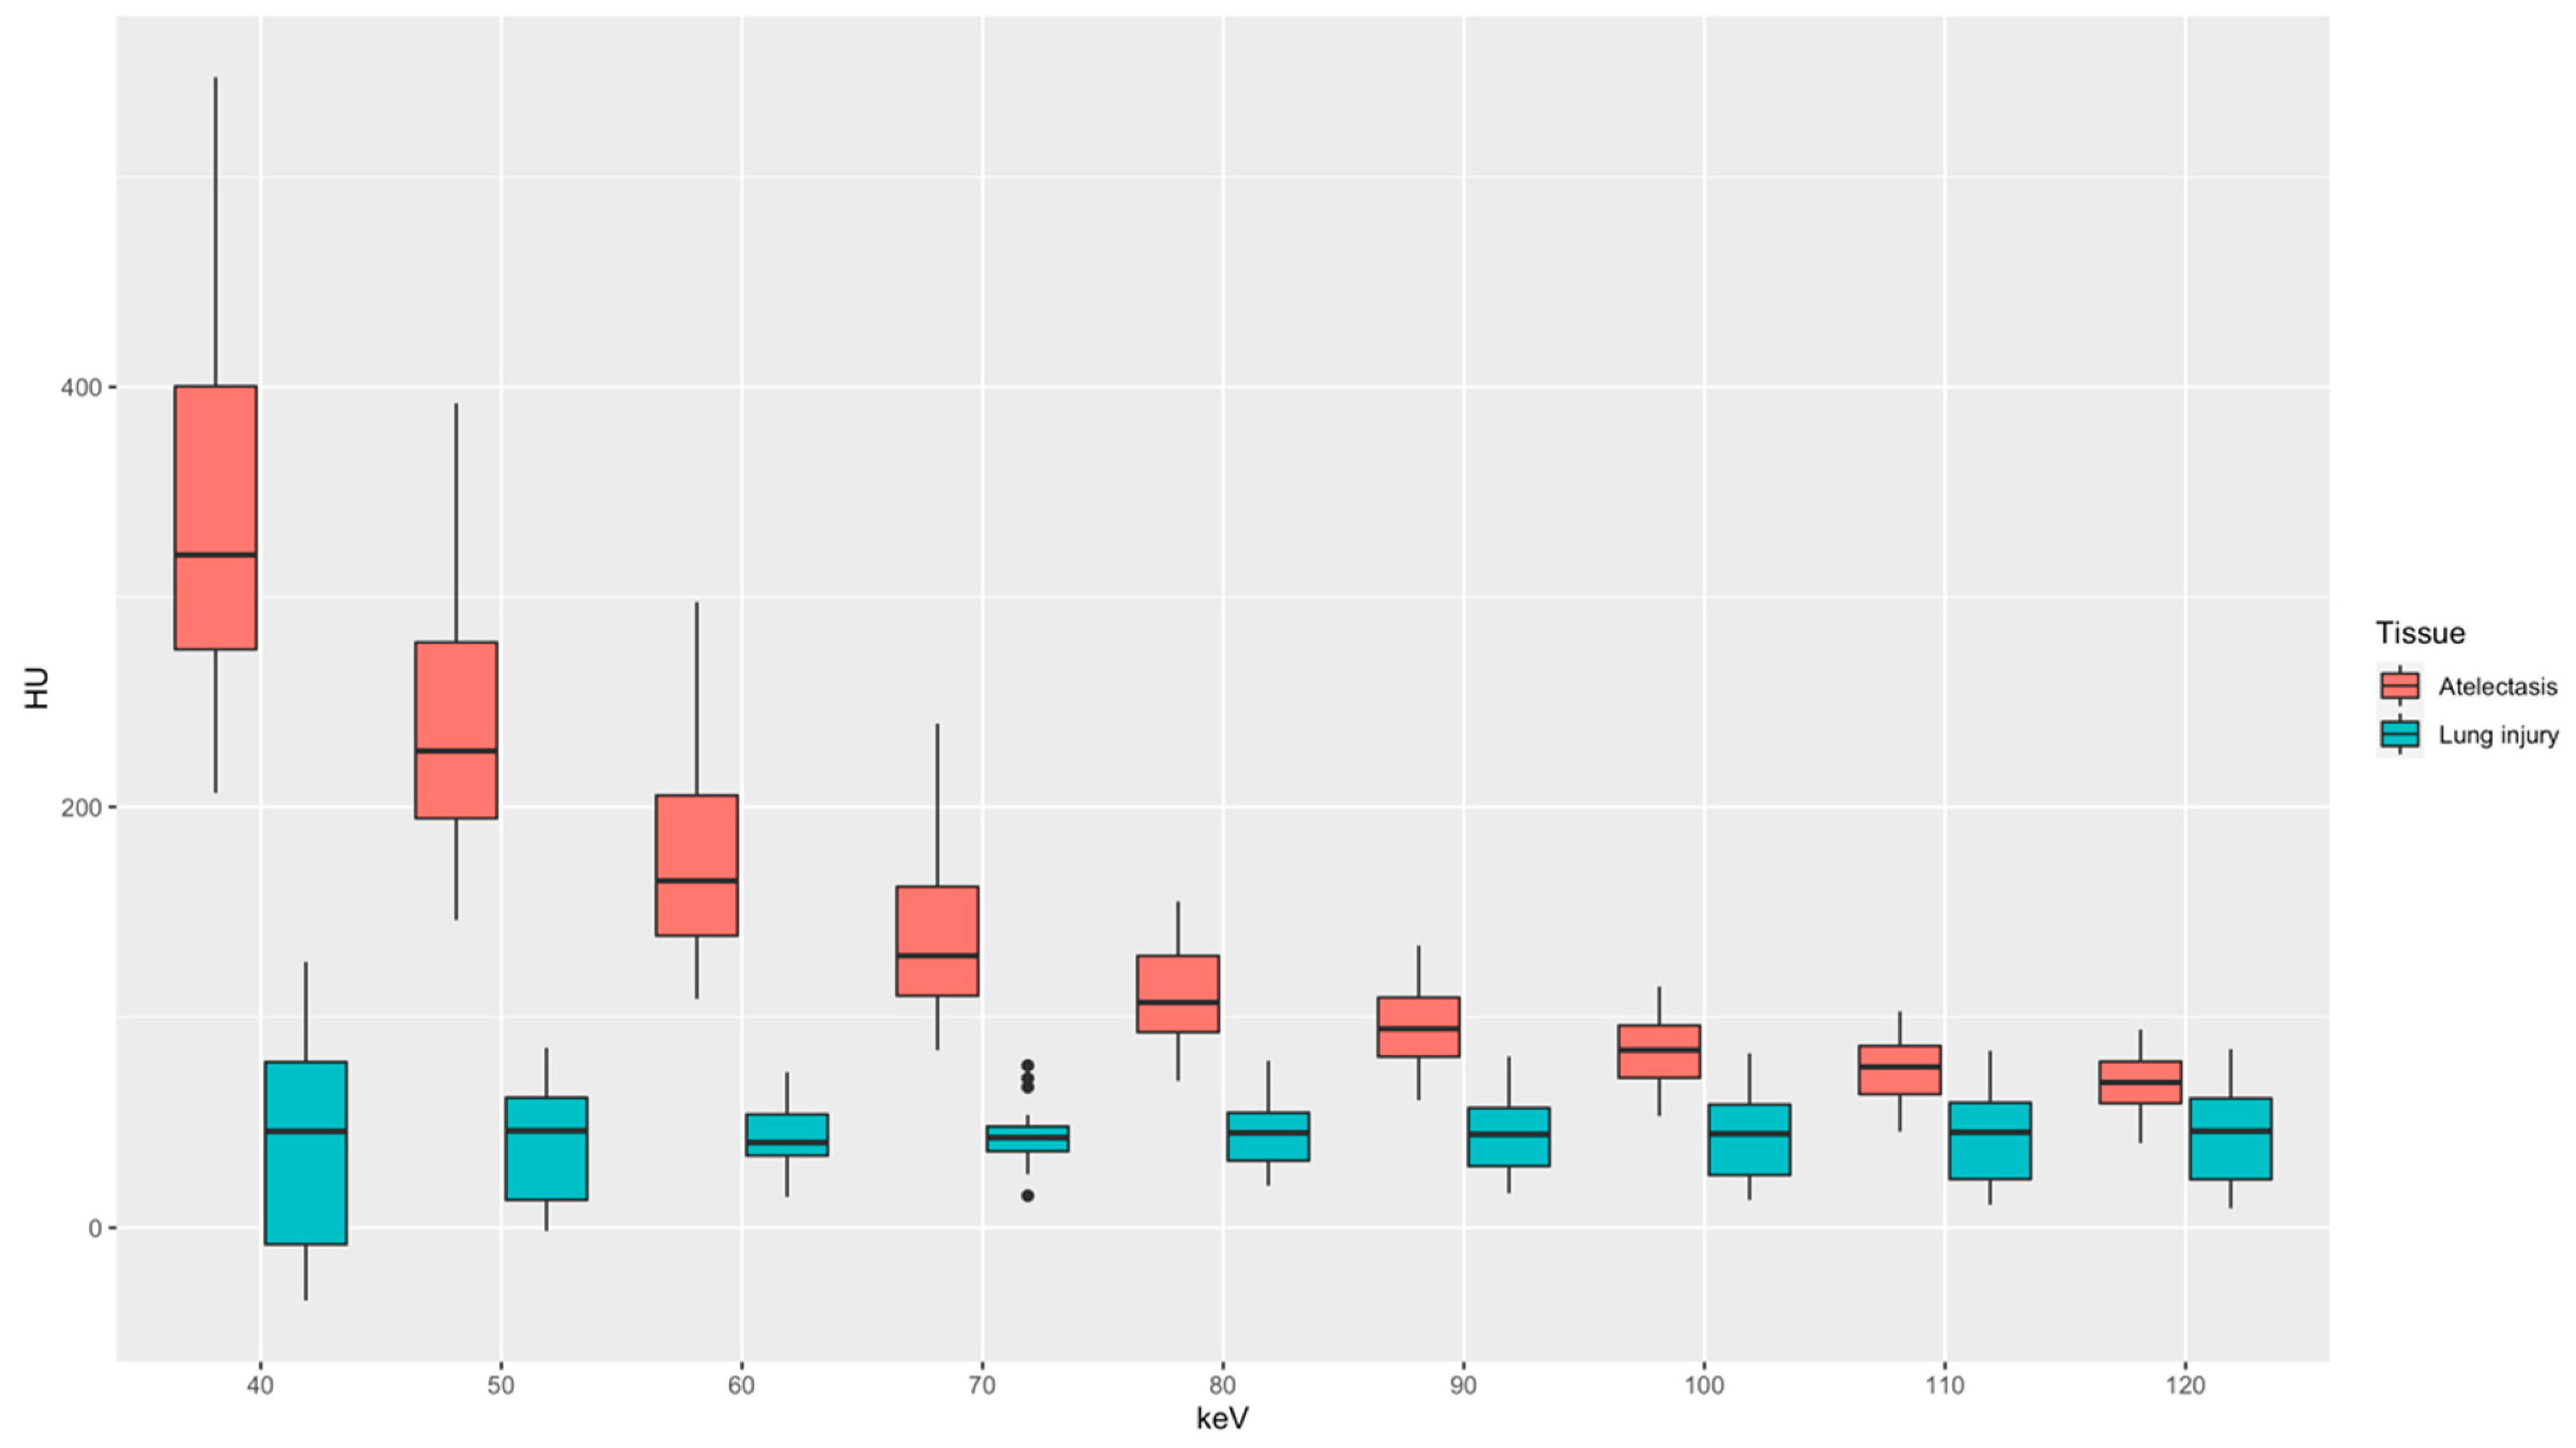

3.2. Quantitative Image Analysis

3.3. Qualitative Image Analysis